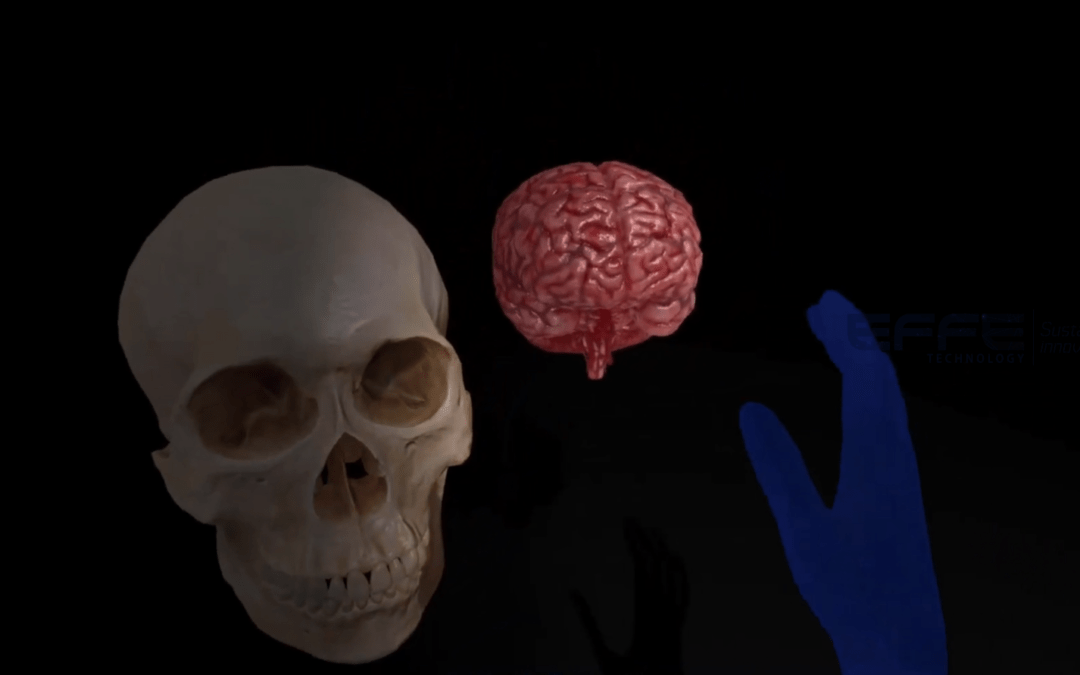

Overview Understanding Brainstem Neuroanatomy is one of the most challenging aspects of medical education. The...

Overview Understanding the human brain—especially the brainstem and intricate neural pathways—requires more than...